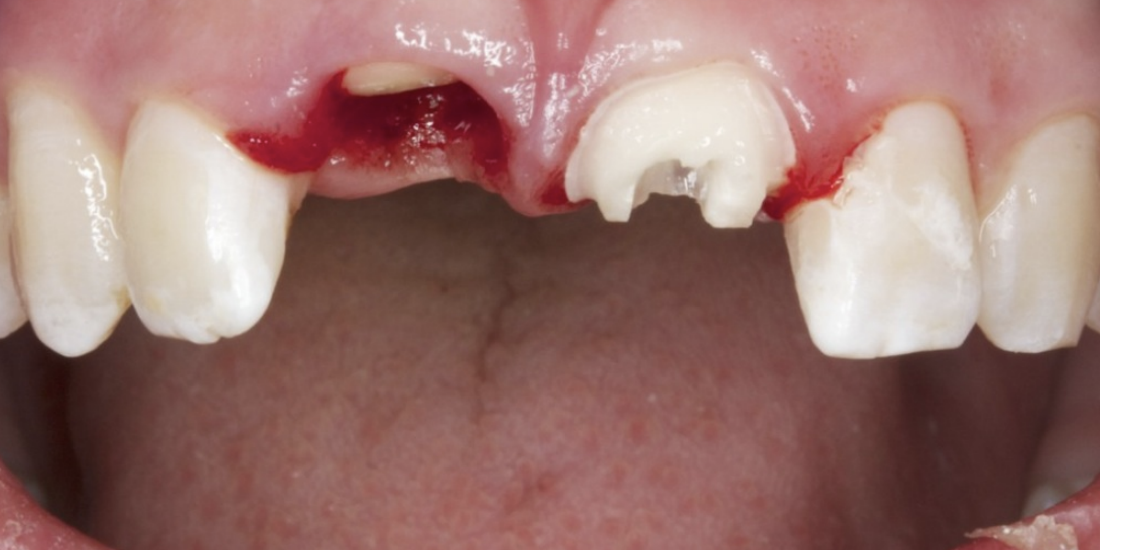

22

Q

abnormalities

A

• right maxillary intrusion and luxation

• left maxillary horizontal fracture involving pulp

How well did you know this?